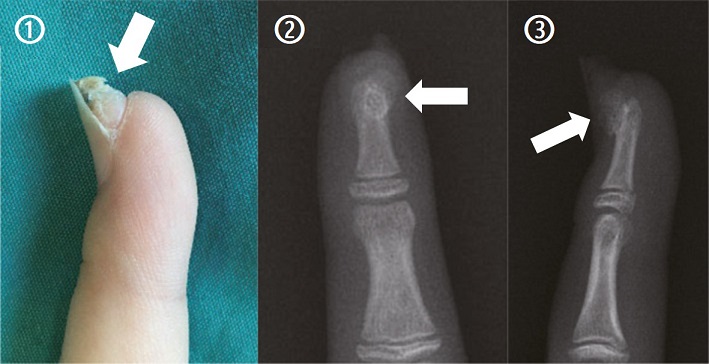

【112-2 醫學(四) 第38題】8歲女童,主訴近兩年來發現右手食指指甲下出現如圖①所示慢慢變大而且會痛的增生物。臨床醫師排了一個X光攝影檢查,結果如圖②③箭頭所示。下列何者是最可能的診斷?